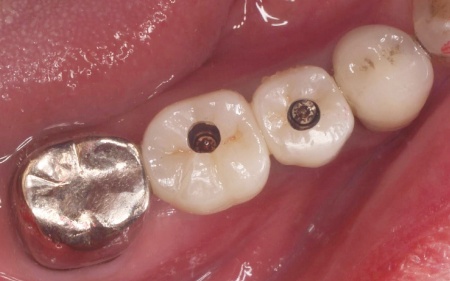

| 行ったご提案・治療内容 | 診断結果を丁寧に説明したうえで、右下奥歯2本の抜歯を提案したところ同意いただきました。 併せて抜歯後に歯を補う方法として、以下2つの選択肢をお伝えしました。 ①前後の歯を削って橋のようにつなげた被せ物で歯を補うブリッジ治療 ②あごの骨に人工の歯根を埋め込み、その上に人工歯を取り付けるインプラント治療 それぞれの特徴や注意点について説明したところ、患者様は②のインプラント治療を希望されました。 まず右下奥歯2本の抜歯を行い、その後、約3ヶ月間歯ぐきや骨が十分に回復するのを待ちました。 |

治療中